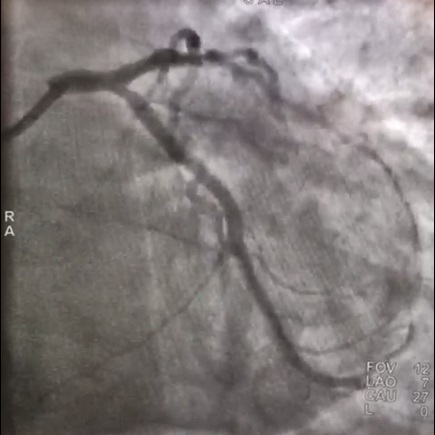

В отделении рентгенэндоваскулярных методов диагностики и лечения Всеволожской КМБ была выполнена экстренная коронарография, которая показала, что несмотря на восстановление кровотока по артериям сердца, имеются критические сужения в правой и огибающей коронарных артериях.

Результаты коронарографии